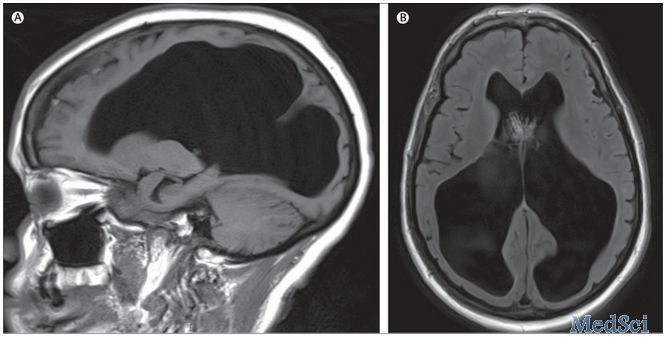

病史概要:女性,62歲,既往有高血壓病史和控制良好的2型糖尿病。被家人發(fā)現(xiàn)倒在地板上無反應(yīng)。家屬指出在入院前病人出現(xiàn)疲勞,虛弱和精神癥狀改變,在此之前一直身體狀態(tài)良好。 入院后,格拉斯哥昏迷評分(GCS)3,體溫39.4°C,心動過速,收縮壓170–200 mmHg。雙下肢無力,但病理征陰性??紤]較低的GCS評分,行氣管插管,但隨后出現(xiàn)了低血壓,高熱,心動過速以及對輸液無反應(yīng),予以使用血管升壓藥物。頭顱CT和MRI顯示大量腦積水。(如圖) 腦MRI無強(qiáng)化,T1和T2顯示大腦幕上和幕下腦室增寬,無中腦導(dǎo)水管異常 治療:腦室外引流可用于緩解可能的急性腦積水,但她的顱內(nèi)壓只有5 mmHg (正常5–15 mmHg)并且保持在5–10 mmHg,所以兩天后撤除了導(dǎo)管。腦脊液 檢查正常??股刂委熀笠庾R狀態(tài)好轉(zhuǎn),結(jié)合胸片和血培養(yǎng),診斷為繼發(fā)于肺炎的膿毒血癥。出院后行康復(fù)治療,現(xiàn)已恢復(fù)至基本狀態(tài)?;仡櫵郧罢5牟∈罚R床團(tuán)隊認(rèn)為她的腦積水從出生之后就有了。 代償性腦積水 定義:代償性腦積水(Compensated hydrocephalus),也稱為“hydrocephalus ex vacuo”,腦脊液空間代償性擴(kuò)大,特征性影像學(xué)改變是腦體積減小導(dǎo)致的腦室或蛛網(wǎng)膜下腔擴(kuò)大。 常將其歸類為交通性腦積水,不阻礙腦脊液的流動,不屬于常見的腦積水范疇。 病理: 常見于老年人,1.由于衰老或疾病導(dǎo)致的腦體積縮小,如阿爾茲海默病,腦白質(zhì)營養(yǎng)不良;2.腦軟化相關(guān)疾病:卒中或創(chuàng)傷性腦損傷導(dǎo)致局部損傷軟化。雖然腦脊液較常人多,但壓力是正常的。 鑒別診斷 腦積水和代償性腦脊液空間增加(腦萎縮)在一些病例中影像學(xué)的準(zhǔn)確鑒別還是有困難的。 影像特點 支持腦積水的特征包括: 顳角擴(kuò)張 海馬周圍裂隙未增寬 額角半徑增加 銳利的腦室角度 室管膜流動引起的腦室周圍間隙水腫 MR顯示腦脊液流動引起的腦室內(nèi)流空影 第三腦室擴(kuò)大:正中矢狀面 胼胝體上部移位:正中矢狀面 后穹窿凹陷:正中矢狀面 視乳頭-腦橋距離減?。赫惺笭蠲?胼胝體角度縮小 扣帶溝跡象 這個病例充分顯示了大腦保持正常意識狀態(tài)和功能的強(qiáng)大調(diào)節(jié)能力,盡管有如此嚴(yán)重的慢性腦積水。與正常壓力的腦積水相比,代償性腦積水可以是無癥狀的,直到出現(xiàn)外部誘因,如這個病例的感染,可導(dǎo)致暈厥甚至突發(fā)死亡。臨床醫(yī)生需注意這種情況可能是在無癥狀患者偶然的體檢中發(fā)現(xiàn)的。在這個病例中,除非有特殊的臨床檢查的需求,是不需要進(jìn)行額外檢查的。